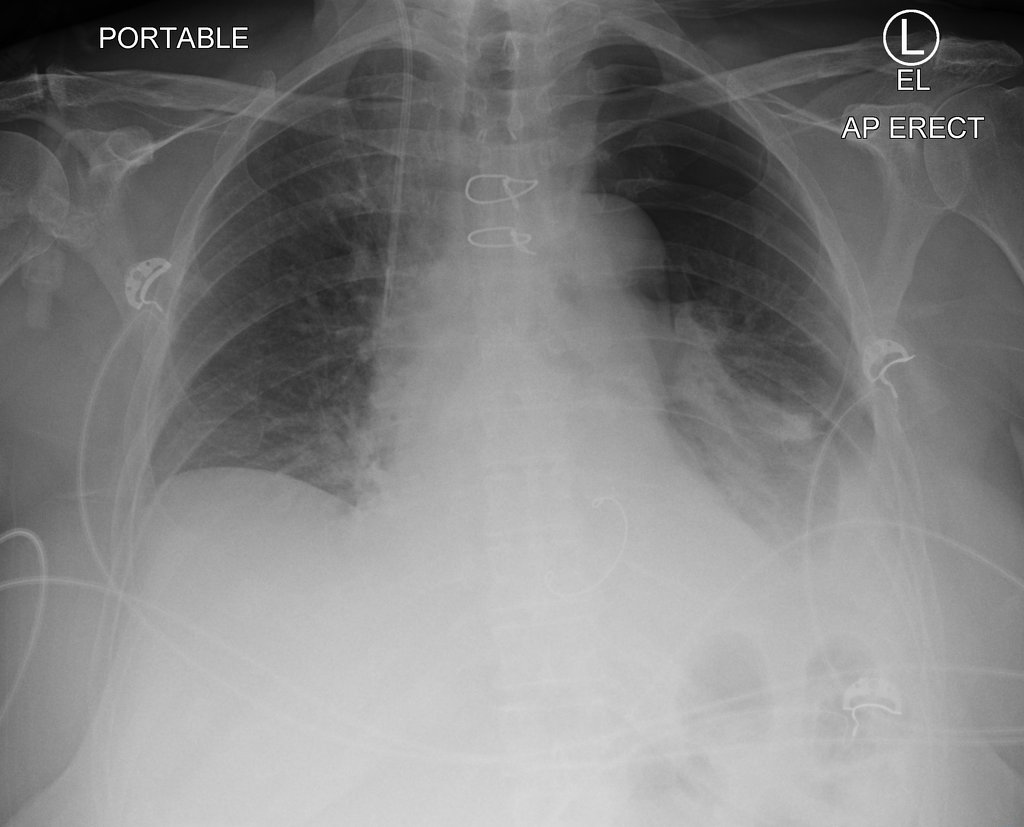

Salut les amis 🎉 Jeune de 35 ans. Douleur thoracique se présentant aux urgences. Onde T sur toutes les dérivations à l'ECG. Votre diagnostic ? 🌐 Interprétation : https://t.co/yh36247Yw8 #Radiologie #EDN